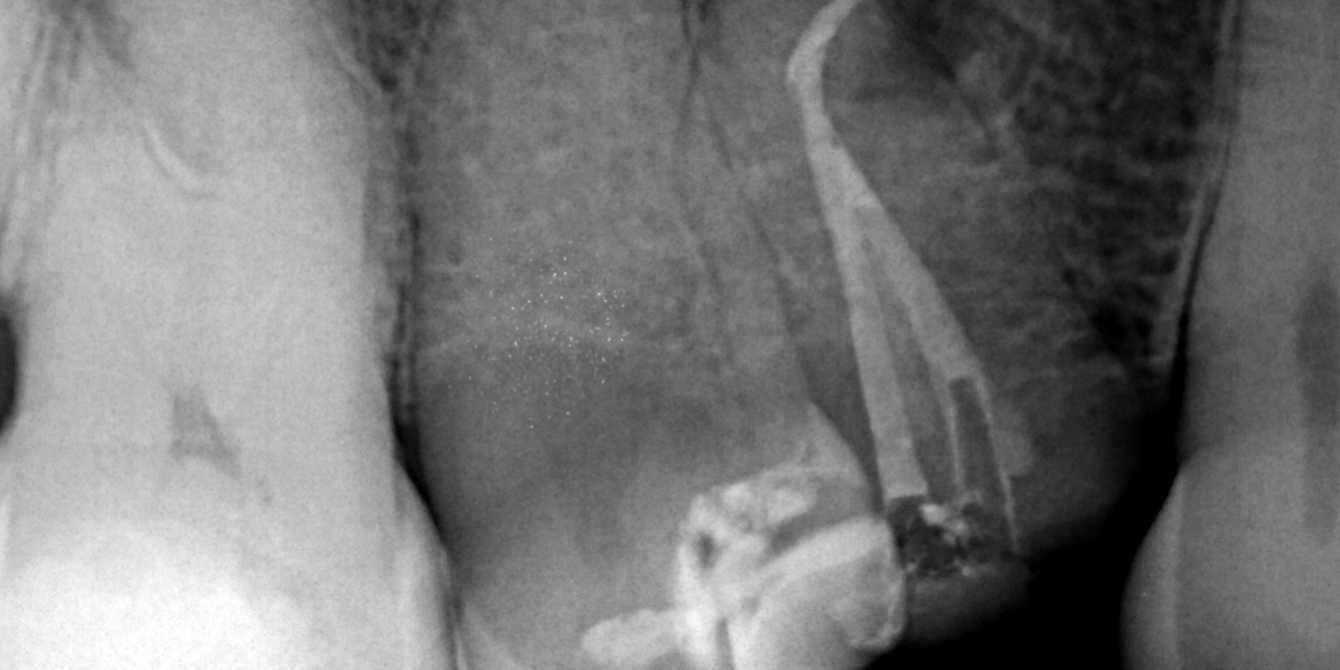

Se empleó BlueShaper®️ y ApicalShaper®️, tecnologías innovadoras diseñadas para facilitar la instrumentación eficiente y segura de los conductos.

BlueShaper®️ es pionero al ofrecer dos tratamientos térmicos únicos: pink y blue, mientras que ApicalShaper®️ está diseñado específicamente para la calibración apical.

Se utilizó una combinación de NaOCl al 5.25% y EDTA al 17%, seguido de NaOCl al 5.25% con una aguja Irriflex, para lograr pasar la curvatura hasta el tercio apical, perfecta para curvaturas abruptas.

Para mejorar la eficacia de la irrigación, se aplicó la tecnología de activación del irrigante con XP EndoFinisher. Esta técnica asegura una distribución homogénea del irrigante en todo el sistema de conductos, maximizando su efectividad en la eliminación de bacterias y detritos.

Obturación con NeoSealer Flo®️:

La obturación del conducto se llevó a cabo utilizando cemento NeoSealer Flo®️ y gutapercha con técnica de onda continua. Esta combinación asegura un sellado tridimensional hermético, previniendo la reinfección y promoviendo la cicatrización periapical.